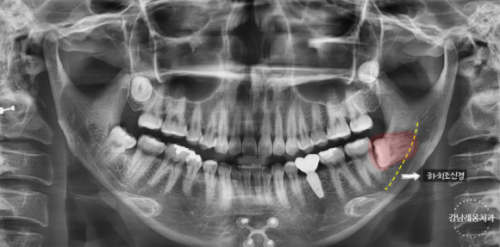

2️⃣파노라마 엑스레이 촬영

엑스레이 촬영을 통해

사랑니 위치와 구강상태를 확인하여

발치 계획을 세웁니다.

(*필요하다면 CT촬영 추가적으로

진행할 수 있습니다.)

Q. 파노라마를 찍었는데 CT는 왜 또 찍나요❓

파노라마 엑스레이와 CT의 기능이 다릅니다.

파노라마 엑스레이로 매복치나

사랑니의 존재 여부는 확인이 가능하나

2차원적인 사진이기 때문에 진짜 주변 구조물과 닿아있는지

아니면 사진상으로만 겹쳐보이는 것인지 확인하기 어렵습니다.

따라서 필요에 따라

3차원적으로 치아를 확인할 수 있는

CT촬영을 진행하게 됩니다.

파노라마 엑스레이 촬영 (2차원)